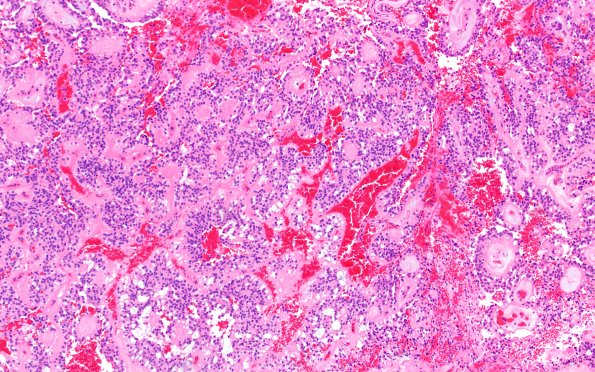

Washington University Experience | NEOPLASMS (GLIAL) | Ependymoma, myxopapillary | 22A1 MPE (Case 22) H&E 10X 1

Case 22 History ---- The patient is a 23-year-old man presenting with low back pain and several enhancing masses in the sacral canal. Operative procedure: S1-S3 laminectomy with decompression and intradural tumor resection. ---- 22A1-4 H&E-stained sections show a well-circumscribed neoplasm composed of mildly pleomorphic cells with eosinophilic cytoplasm and slightly distinct borders which are organized around papillae with fibrovascular cores. Most of these papillae envelop nests of myxoid material. Mitoses are present (up to 2/10 HPF) but not abundant. (H&E)